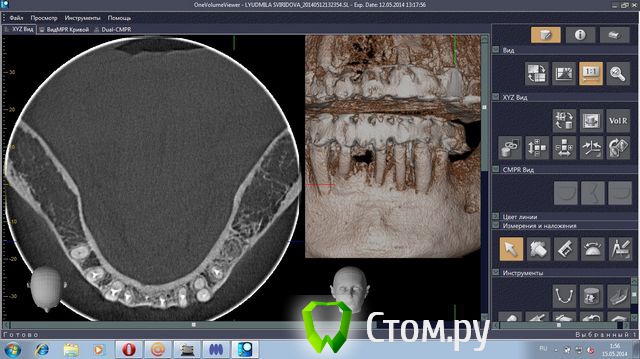

stradalitca Опубликовано 18 мая, 2014 Поделиться Опубликовано 18 мая, 2014 Здравствуйте! у меня проблема такая. за последние 4 года мне удалили нижний центральный зубик (киста была), пролечили каналы в нижних зубах. Поставили мост с металлокерамики. Он простоял некоторое время, а потом( год-два) просто стал качаться. Его раза три сажали заново на цемент( прошлым летом). в итоге, пошла в другую клинику. Мост ещё раз сняли( он держался на честном слове). Оказалось, что пятёрка снизу слева пробита вкладкой. Зуб удалили. На сдедующий день обточили ещё зубы некоторые и сняли слепок под новые пару вкладок. через неделю поставили на цемент( сразу на цемент, без времянки)НОВЫЙ мост. Это было в конце декабря. Через две недели десну разнесло и прищлось резать, выпускать гной( надрез примерно под тройкой слева). Сейчас опять явный свищ примерно под 3-4 нижними слева.Сделали рентген - оказалось, что тройка имеет два корня и она пробита вкладкой. Теперь даже не знаю что делать. Просто резать десну и опять чистить? Врач говорит, что надо снять мост и удалить тройку. Другой врач говорит, что тройку может и можно спасти, надо снять мост, убрать вкладку и смотреть, что с тройкой. На прошлой неделе сделала объёмный рентген. Сама неделю копалась в программе, разглядывя свою нижнюю челюсть. мне показалось, что там маячит какой-то остаток корня шестёрки слева( мне его сто лет назад удаляли). Пожалуйста, подскажите, что делать? какие перспективы и варианты есть на мои нижние зубы?Заранее большое спасибо за все ваши ответы и мнения.Скриншоты с программы 3D прилагаю.или может надо мост снять, выдернуть тройку слева и поставить металлопластмассу?( верхние зубы тоже штук 8 слитно металлокерамика, ставили первый паз отдновременнно нижние и верхние) Ссылка на комментарий

stradalitca Опубликовано 20 мая, 2014 Автор Поделиться Опубликовано 20 мая, 2014 (изменено) Добрый вечер! Я тут ещё глянула как установлен штифт на четвёрке снизу справа. Вот фото в проекциях. Неужели зуб тоже пробит штифтом? или пойдёт ? и я зря переживаю. Изменено 20 мая, 2014 пользователем stradalitca Ссылка на комментарий